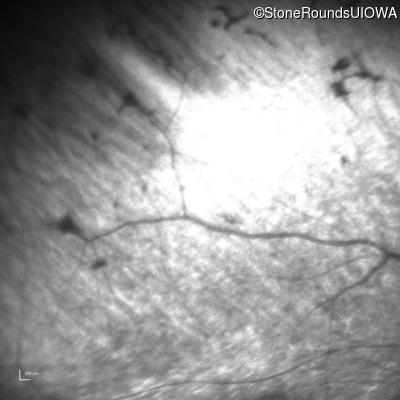

Infrared Fundus Photograph - Right - No Light Perception

Exemplar